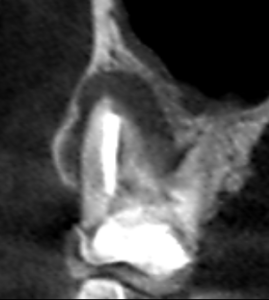

上顎大臼歯の矢状断のCT画像です。

赤い矢印の先に黒い大きな膿の影がみられます。